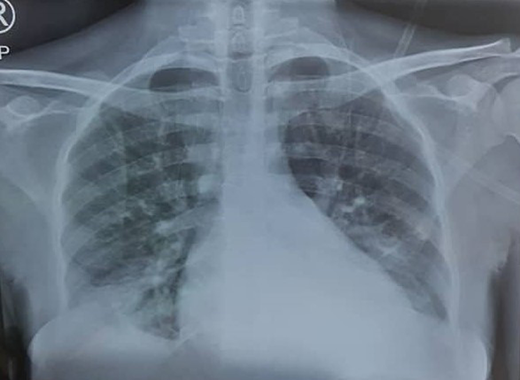

Chest radiograph (PA view) showing pulmonary infiltrates classic to ACS.

The patient's chest x-ray showed radiopacities (Figure 1). Despite an increase in the oxygen flow rate, the twice-daily administration of 1 g of ceftriaxone, and a simple transfusion of 3 units of packed RBCs (PRBCs) within 24 hours, her Hb level only increased to 6.2 g/d, and she remained oxygen dependent. She subsequently had a manual exchange blood transfusion (EBT) with 6 units of ABO Rh D-compatible HbS-negative PRBCs that were less than 7 days old as per the unit protocol. Her postexchange Hb concentration was 8.6 g/dL, and her HbS fraction was 22.3%.

ACS, an important complication of SCD, is characterized by fever and/or respiratory symptoms and a new pulmonary infiltrate on chest x-ray. It is a significant cause of mortality and is frequently seen in pregnant women, with 4 out of 5 deaths in a series of 71 Hb SS women with 177 pregnancies.7 ACS caused nearly 87% of the maternal deaths in a multicenter case series in Ghana.17